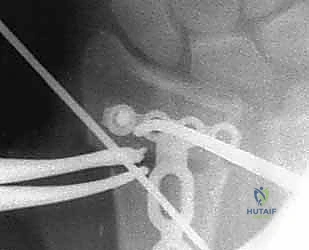

5. التثبيت بصفائح التيتانيوم (Internal Fixation)

للحفاظ على الوضع الجديد والمثالي للعظم، يتم استخدام صفائح تيتانيوم متقدمة ذاتية الغلق (Volar Locking Plates). هذه الصفائح مصممة تشريحياً لتلائم شكل الكعبرة، وتوفر تثبيتاً قوياً جداً يسمح للمريض ببدء تحريك أصابعه في اليوم التالي للعملية.